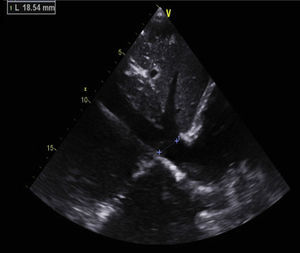

Antiphospholipid syndrome (APS) is an autoimmune disease, with antiphospholipid antibodies associated with hypercoagulability, vascular thrombosis, and fetal loss.1,2 Cardiac involvement occurs frequently, and is deeply related to hypercoagulability in spite of recommended anticoagulant therapy.3 In this report, we describe the images of a Caucasian 19-year-old male, with a previous history, 4 years earlier, of an acute in situ right chamber thromboembolic episode submitted to a surgical intracardiac thrombectomy. At this time APS was diagnosed with increased levels of lupus anticoagulant and IgM anti-beta(2)-glycoprotein I. All other autoantibodies were negative. He was readmitted in April 2012 with an initial suspicion of endocarditis. Intracardiac and inferior vena cava thrombi as well as acute and chronic pulmonary thromboembolism were detected in spite of adequate anticoagulation. After full dose anticoagulation he improved well and was discharged. In September 2012 he was readmitted after 2 weeks of fever, dyspnea and left thoracic pain again with pulmonary thromboembolism. Transthoracic echocardiogram (TTE) revealed an image suggestive of a thrombus at the upper part of the atrial septum in the right atrium (25×8mm), Image 1, and in the inferior vena cava (18mm) near the roof of the right atrium, Image 2. Also in the infundibulum of the right ventricle and in the right ventricular outflow tract several freely moving masses were visualized, indicative of thrombus near the lateral wall, Image 3. A long course of antibiotic was done and all microbiological tests proved negative. Hydroxychloroquine and colchicine were added to an intensive antithrombotic regimen of acenocumarol, enoxaparin and acetylsalicylic acid with a significant reduction of the right atrium and inferior vena cava thrombi and a complete disappearance of the right ventricular masses. The patient improved clinically and no further relapses were observed during follow-up.